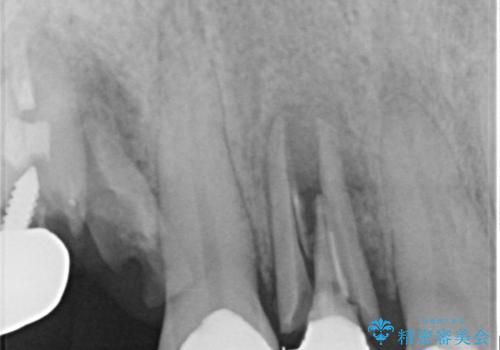

- 歯が破折しているため、抜歯が必要であると近医で診断されてからも放置を続けてしまったとのことで来院された患者様です。

臼歯はもはや咬み合わせに寄与していない状態であり、3歯を抜去してインプラント2本埋入によるブリッジ補綴を計画しました。

セオリーとしては、インプラント補綴治療により奥歯の咬み合わせを確立してから、前歯部の処置を行うことになりますが、初めてのインプラント治療であることや、前歯部の見た目が気になっていることから、前歯の抜歯即時埋入インプラントによる補綴治療を先行して行い、並行して奥歯のインプラント治療を進めて行くこととしました。

抜歯即時埋入インプラントによる補綴治療の特徴は、短期間であることや処置数が少ないことが挙げられます。また、表側の歯肉の陥凹を避けることができるというメリットがあります。しかしながら、今回は歯根破折の程度が酷く、やや膨らみを失うこととなりましたが、スムーズに治療を終えることができました。

臼歯部は前歯以上に炎症が酷く、抜歯即時埋入不可と判断されましたが、従来法よりは短期間で終えることができました。